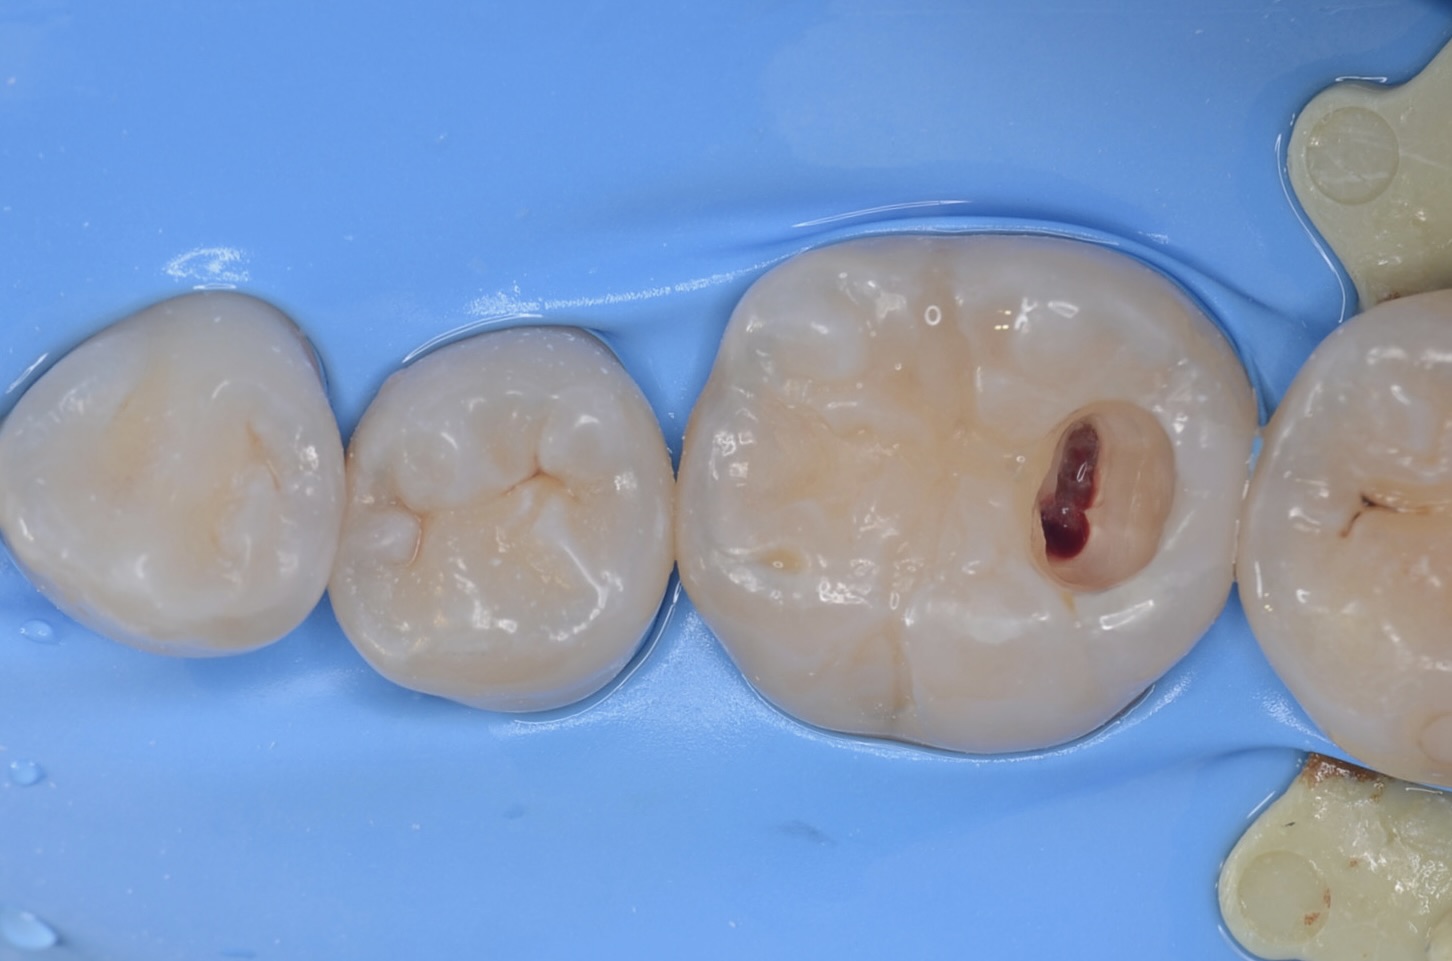

露髄

1週間後に治療の続きをします。 完全に虫歯を取り切ると露髄しました。 -